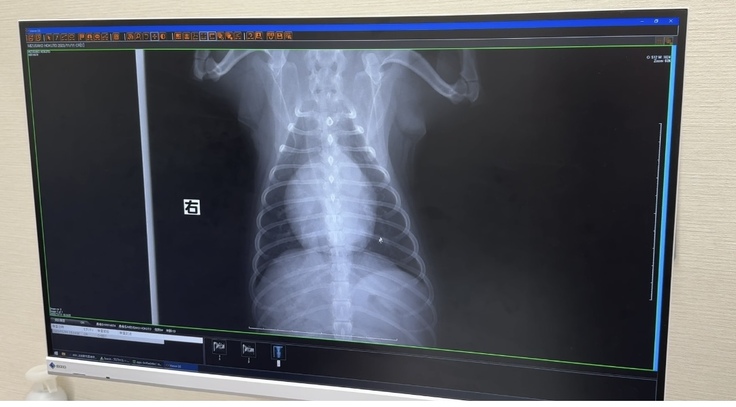

▽レントゲン写真

心臓が大きくなってしまってます

(通常の大きさが1.6以下なのですが、ほくとの場合2になってしまってます)